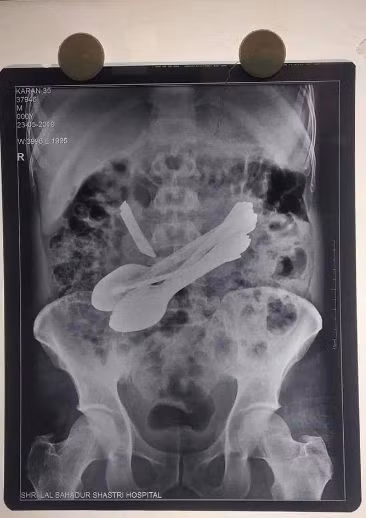

Các bác sĩ sau đó đã tiến hành phẫu thuật để loại bỏ những vật thể lạ trong bụng của Karan. Bác sĩ vô cùng choáng váng khi lấy ra được tổng cộng 14 vật thể trong dạ dày của người đàn ông này, bao gồm 8 chiếc thìa, 2 chiếc tuốc nơ vít, 2 bàn chải đánh răng, 1 con dao làm bếp và 1 chốt cửa.

14 vật thể trong bụng của người đàn ông.